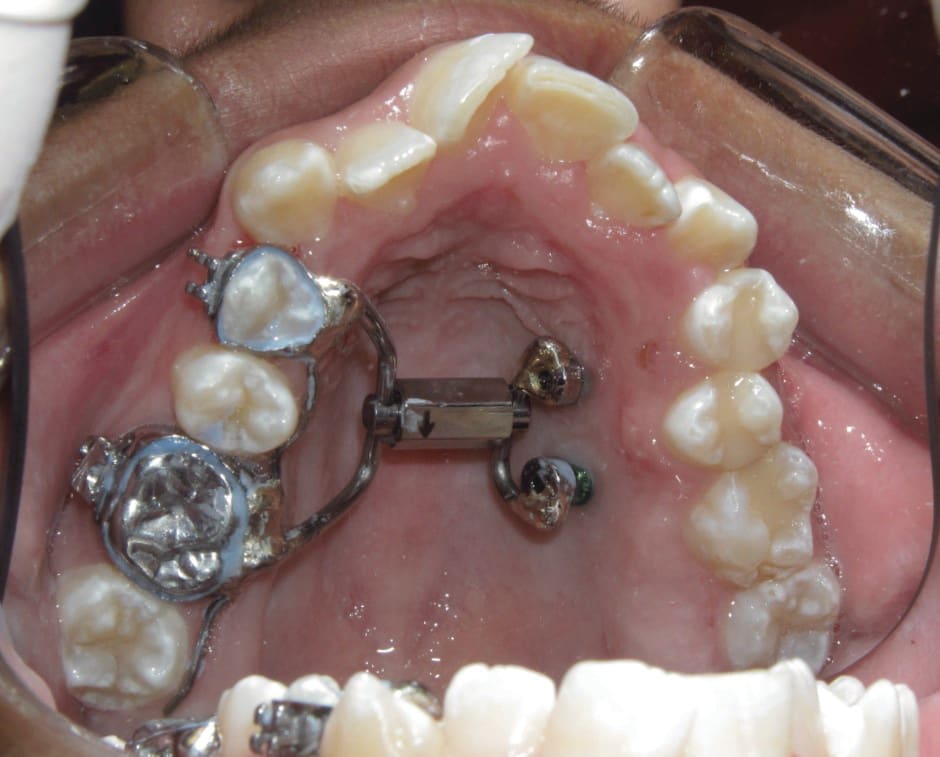

5. Any case that needs expansion of the maxilla. 3D imaging in these cases allow the orthodontist to determine if a cross bite is skeletal or dental. The clinician can readily determine if the molars are inclined in a cross bite or if the entire maxilla is constricted. This in turn can determine what forces are desirable to correct the cross bite. The 3D images also allow the clinician to evaluate the amount of bone around the roots of the teeth that are to be expanded. This also can aid the orthodontist in the type of forces to be utilized. Maybe bone augmentation is indicated in certain areas so as the roots are not once again fenestrated through the cortical bone creating a less stable environment. See Figure 18 through Figure 25. Figure 18 illustrates a maxilla that is constricted due to a narrow maxilla. Figure 19 illustrates the maxilla after expansion. Figure 22 illustrates a molar being tipped lingually. Thus a unilateral cross bite appliance was utilized.